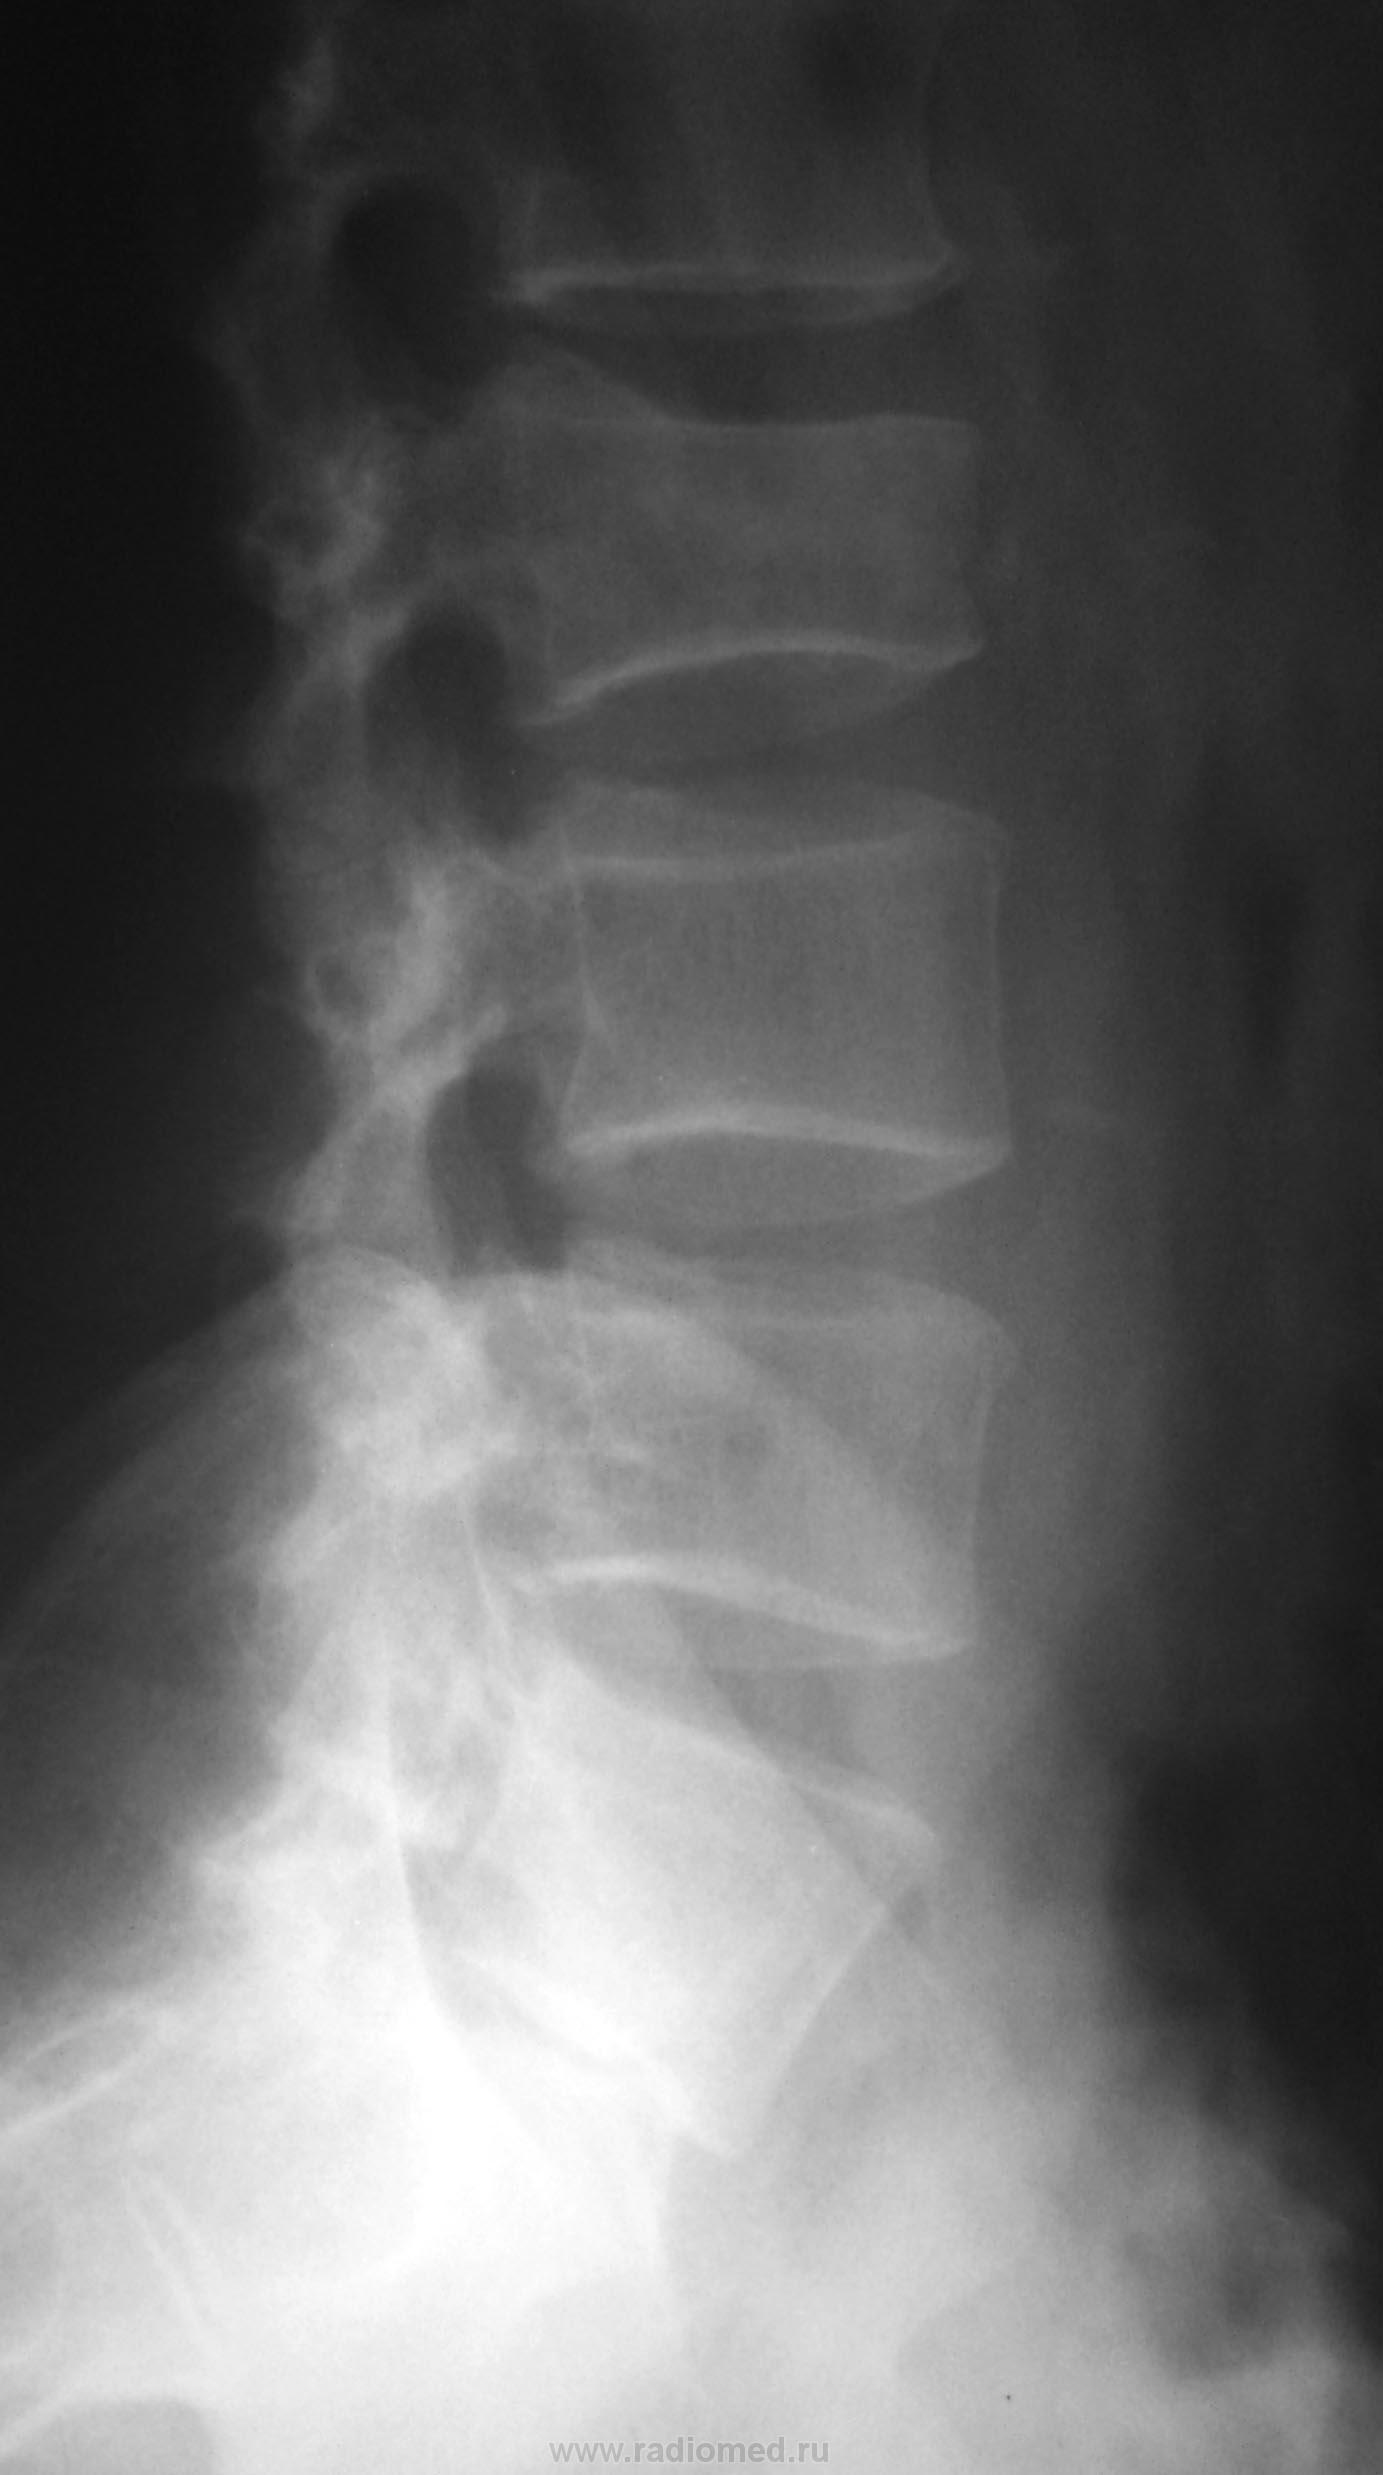

Мужчина с 1971 года рождения, очень давно попал в ДТП... Что с крестцом, неоартроз?

Да, неоартроз. Позвонки бы еще получше посчитать. Сколько их, поясничных?

Поперечная линия (на прямой рентгенограмме) справа конечно видна, но создается впечатление, что "несвежак"....

В ветке задан вопрос по поводу крестца..., и где тойный крестец? Крестец так не "рентгенографируют".

От крестца, особенно на боковой, сомнительный огрызок...

Вот симбиоз Л5 с крестцом мне не понятен, плохо проработана боковая, косвенно похоже на антелистез, но "зуб" не дам...

Рентгенограмму делали на поясничный отдел, так как задача стояла в исключении перелома L3, изменения в крестце случайная находка.

А "сплюснут" Л2....?

Компрессионный перелом L3....нет, всё ж L2

Компрессионная деформация L2, перелом боковой массы крестца справа с исходом в неоартроз.

Как-то нет убежденности, что это "второй" позвонок.

Вы правы, ребер для полного удовлетворения не хватает...

У меня получился третий.

Еще как при делах. Именно неясность  с L5/S1 наводит на мысль об аномалии/варианте развития.

Переходный позвонок. А вот какой: поясничный или крестцовый?

Переходный позвонок с признаками люмбализации (наличие диска между ним и нижележащим крестцовым позвонком, а также свободный левый поперечный отросток), и сакрализации (сильно гипертрофированный правый поперечный отросток с формированием неоартроза между ним и крестцом).

И еще: Вопросик о счете поясничных позвонков. откуда их считать? Сверху? Снизу?. если сверху то как оценивать Тh12 без последней пары ребер? (Думаю что делать снимки грудного отдела просто для подсчета - незачем) Кстати, в данном случае, вверху снимка в прямой проекции виден позвонок без ребер - возможно что он будет L1, тогда поясничных позвонков 6.

Люмбализация 1 крестцового позвонка, соответственно- компрессионный перелом 3 поясничного позвонка.

Говорил уже много раз, повторюсь, пожалуй - переходный, ассиметричный, неподвижный, с образованием неоартроза справа, пояснично-крестцовый позвонок (это для данного конкретного случая).

Чтобы "не впутывать сюда ни "люмбализацию", ни "сакрализацию", так что "третий", Андрей Юрьевич сразу об этом намекнул, а потом и сказал)))